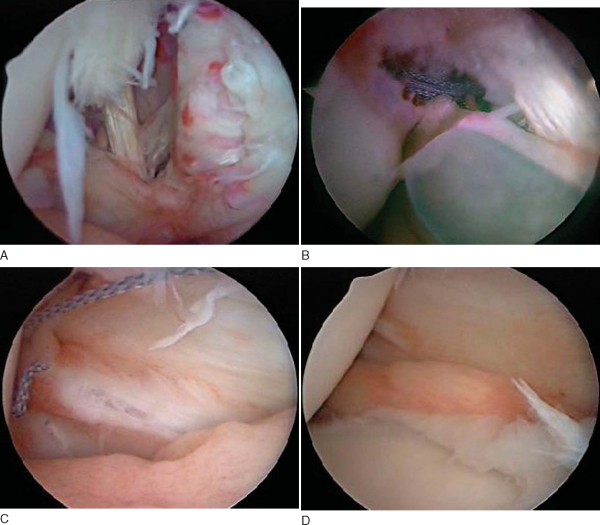

Diagnostic arthroscopy usually reveals the pathologic process. Most of these are readily apparent once the arthroscope is placed within the joint. The avulsion of the Buford complex attachment is the most difficult to differentiate from normal variants. Chondromalacia of the glenoid and fraying of the undersurface of the labrum and outer surface of the glenoid isolated to that area alone and not farther inferior on the glenoid are key findings (

Fig. 7-3

).

Traumatic chondral defects and osteochondritis of the humeral head or glenoid result in irritation and swelling within the glenohumeral joint. Finding these loose articular pieces within the shoulder joint and their removal will help decrease symptoms (

Fig. 7-7

). The injured bed in the articular surface should also be located and débrided and at least marrow stimulation performed.

Humeral avulsions of the anterior glenohumeral ligaments are covered elsewhere in this text. However, one may occasionally find this lesion in conjunction with a Bankart lesion (

Fig. 7-9

). In these cases, the Bankart lesion is repaired first, and then the humeral avulsion is repaired. This also represents an excellent indication for open surgery by Matsen’s approach to elevate the lateral subscapularis and use the humeral avulsion to access the Bankart lesion. The capsulolabral complex is repaired to the glenoid, and the humeral avulsion is repaired as part of the reattachment of the lateral capsule and subscapularis tendon.

Figure 7-9 |